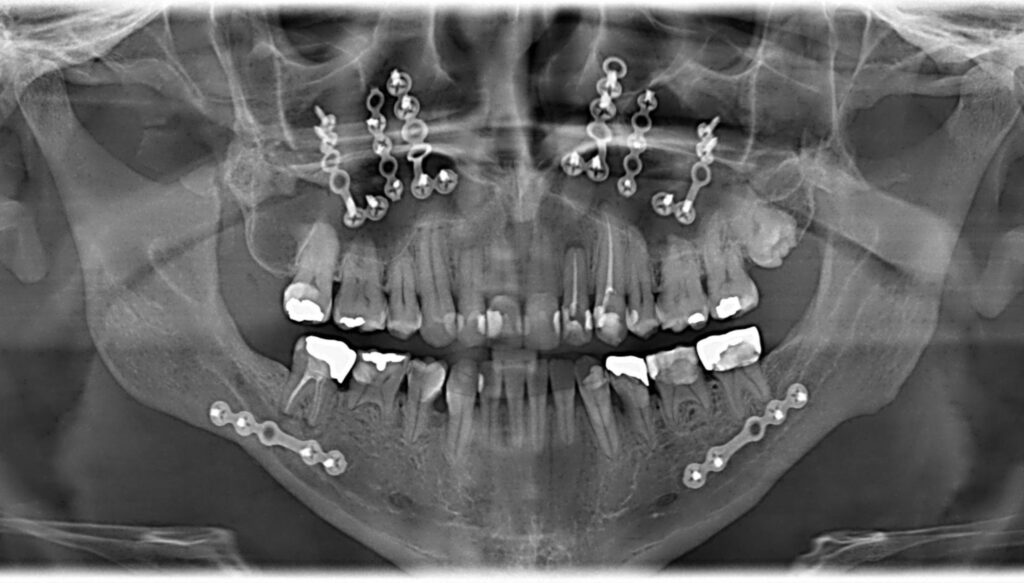

W Dynasty Stomatology każdy etap leczenia — od zaawansowanej diagnostyki obrazowej (CT, tomografia, RTG stomatologiczne) po sterowaną regenerację kości, podniesienie zatoki szczękowej, podniesienia dna zatoki szczękowej i odbudowę protetyczną — odbywa się w jednym miejscu. Bez skierowań, bez dodatkowych dojazdów. Twoja operacja w obrębie jamy ustnej jest planowana i wykonywana przez jeden zespół pod jednym dachem, z pełnym dopasowaniem do Twojego stanu zdrowia i potrzeb.

Chirurg stomatolog przeprowadza dokładne badanie, w tym tomografię 3D (CT), aby ocenić objętość tkanki kostnej i precyzyjnie określić obszar wymagający interwencji. Nasz specjalista dokładnie analizuje stan Twojego uzębienia, w tym okolice wierzchołka korzenia, by zaplanować bezpieczny i skuteczny zabieg.